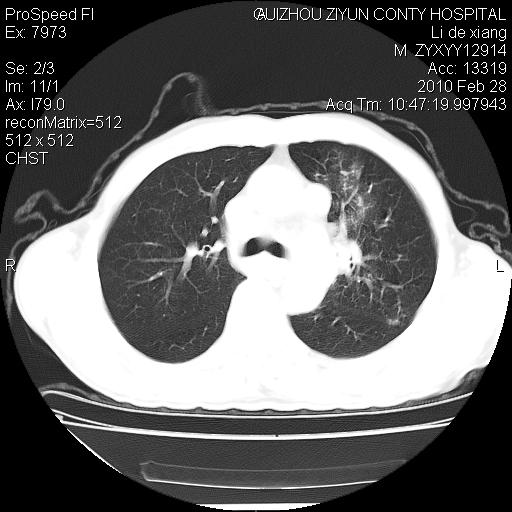

标题: CT24776:男 71Y 咳嗽咳痰胸痛两月,伴声音嘶哑。 [打印本页]

标题: CT24776:男 71Y 咳嗽咳痰胸痛两月,伴声音嘶哑。

左侧中央型肺癌伴左肺上叶阻塞性肺炎及节段性不张可能性大,建议纤支镜检查!

左侧中央型肺癌伴左肺上叶阻塞性肺炎及节段性不张可能性大,建议纤支镜检查!纵隔淋巴结转移.

左肺门部肿块,伴左上肺斑块影,周边模糊,支持左肺中央型肺癌伴节段性不张及阻塞性肺炎,结合支气管镜检查。

左上叶支气管狭窄,阻塞性病变,肺门肿块,纵隔及肺门淋巴结增大,中央性肺癌

左肺中央型肺癌并阻塞性改变、纵膈 淋巴结转移

左侧中央型肺癌伴左肺上叶阻塞性肺炎及纵隔淋巴结转移